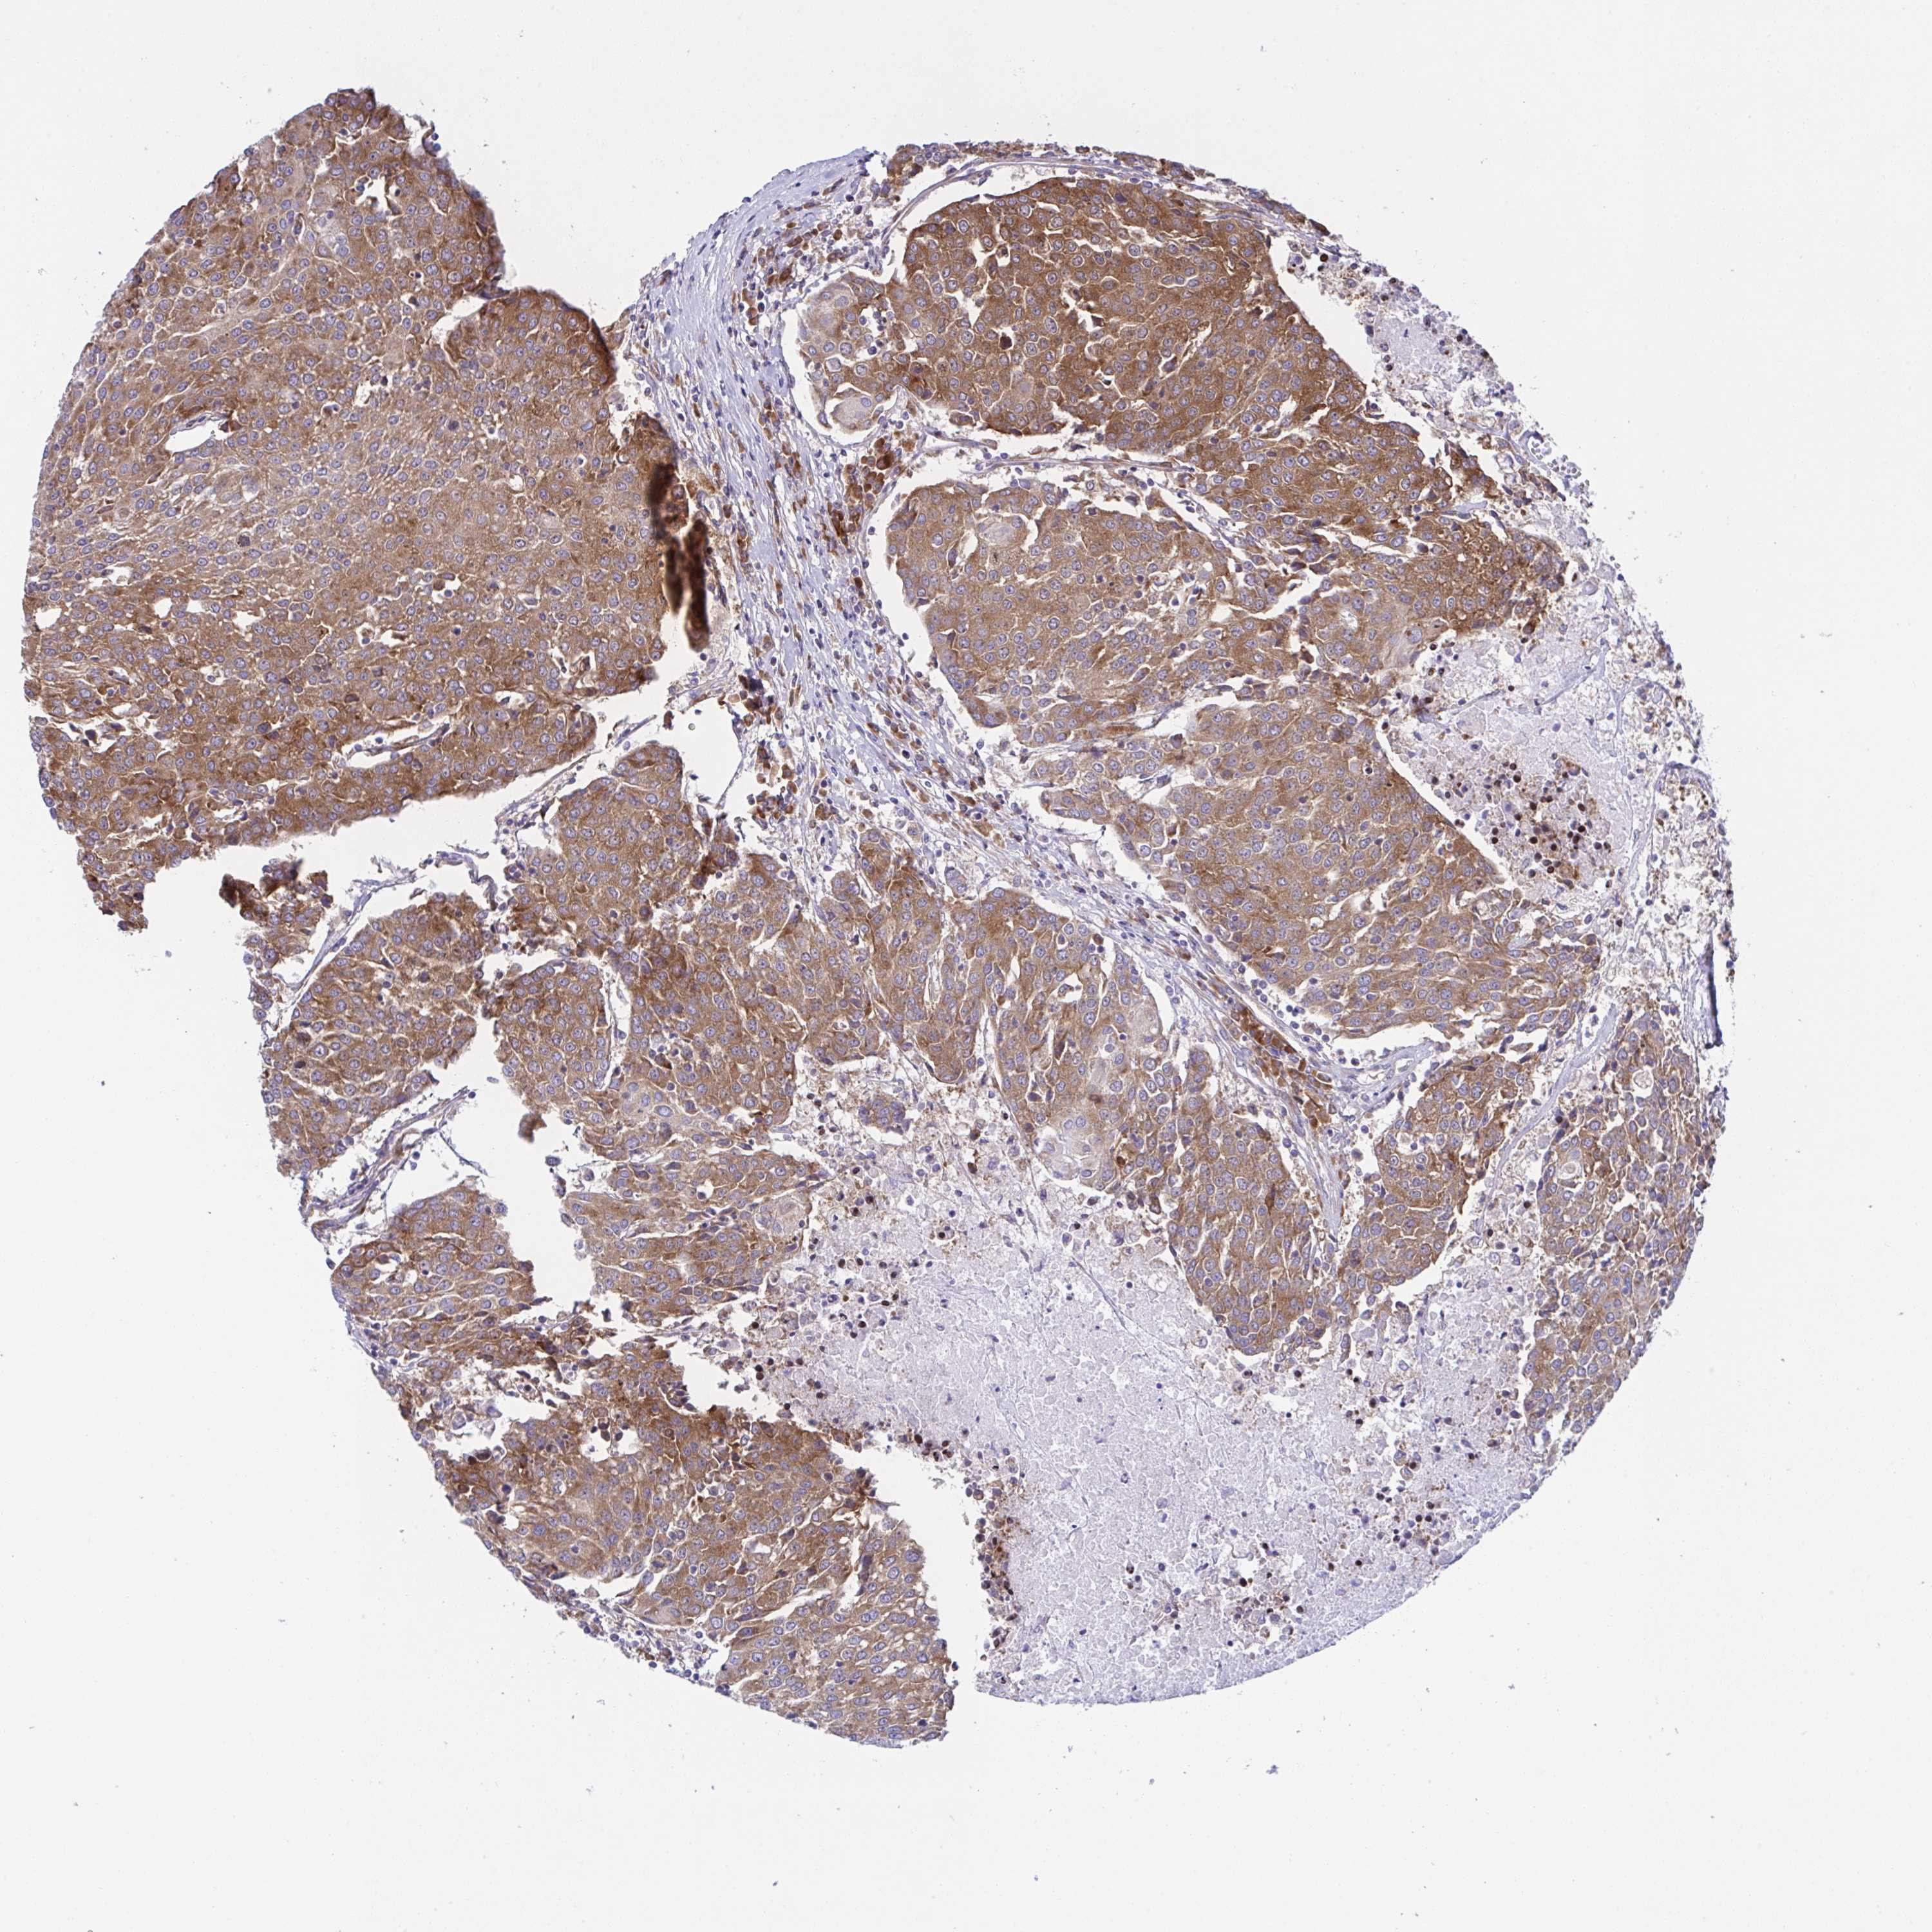

UROTHELIAL CANCER - Protein expressioni

A mouse-over function shows sample information and annotation data. Click on an image to view it in a full screen mode. Samples can be filtered based on level of antibody staining by selecting one or several of the following categories: high, medium, low and not detected. The assay and annotation is described here.

Note that samples used for immunohistochemistry by the Human Protein Atlas do not correspond to samples in the TCGA dataset.

Antibody stainingi

Antibody staining in the annotated cell types in the current human tissue is reported as not detected, low, medium, or high, based on conventional immunohistochemistry profiling in selected tissues. This score is based on the combination of the staining intensity and fraction of stained cells.

Each image is clickable and will lead to virtual microscopy that enables deeper exploration of all samples and also displays staining intensity scores, fraction scores and subcellular localization as well as patient and tissue information for each sample.

Antibody HPA059015

Staining

High

Medium

Low

Not detected

Intensity

Strong

Moderate

Weak

Negative

Quantity

>75%

75%-25%

<25%

None

Location

Nuclear

Cytoplasmic/membranous

Cytoplasmic/membranous,nuclear

Urothelial carcinoma, High grade

Urothelial carcinoma, NOS

Urothelial carcinoma, Low grade